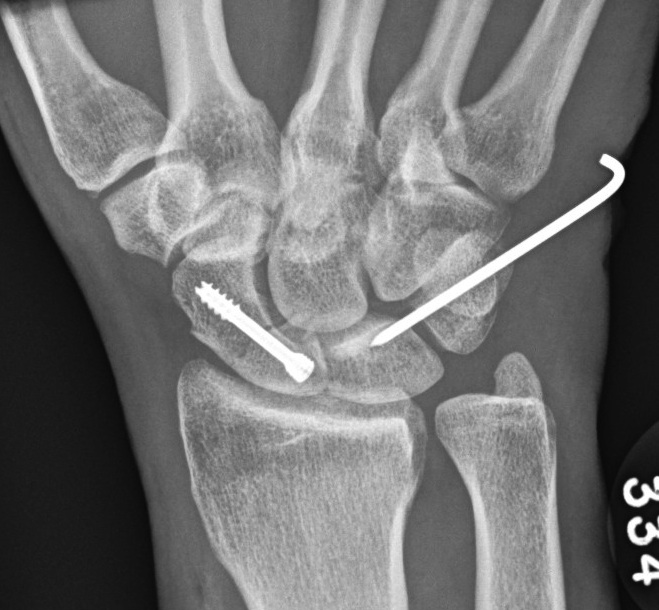

2. Trans Scaphoid Perilunate

Dorsal approach

- ORIF scaphoid fracture

- repair LT ligament

- K wires LT and TC (SL ligament is intact)

- ORIF capitate

+/- Volar approach

- CTD

- repair rent in capsule